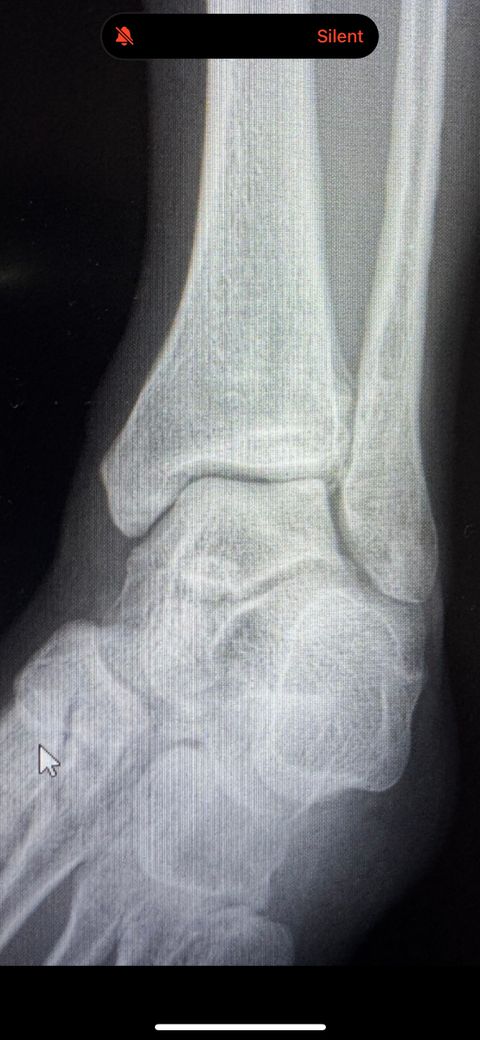

사진도 첨부합니다

2번 사진은 발을 약간 안쪽으로 굽은 상태에서 찍은 사진 입니다.

• 2번 째 사진

사진상으로는 정확한 상태 파악이 어렵지만 외상 후에 염증과 관절면 변화가 보이며 외상성 관절염의 초기 증상을 의심해볼 수 있을 것 같습니다. 정확한 상태 확인을 위해 재검사를 받아보시는 것도 좋을 것으로 생각됩니다.

외상 후에 염증과 관절면 변화가 보이면 외상성 관절염 초기로 볼 수 있습니다. 다만 병무청은 일시적 염증과 구조적 변화를 구분해 후자를 기준으로 인정해요 정밀 검사나 추가 영상에서 연골 손상 골극 등 확정 소견이 있으면 인정 가능성이 높아집니다!